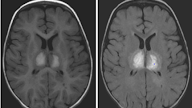

abnormal mri brain Ependymitis

• —Ventriculitis, or ependymitis, is an inflammation of the ependymal lining of the ventricular system

Gadolinium-enhanced MRI studies show thin, smooth ependymal enhancement in an AIDS patient with cytomegalovirus ependymitis

—The differential diagnosis on CT and MRI studies includes ependymal seeding of intracranial neoplasm. The ependymal enhancement may be irregular or nodular if it is secondary to seeding of neoplasm, the clinical history may be helpful in arriving at the correct diagnosis. see below images.